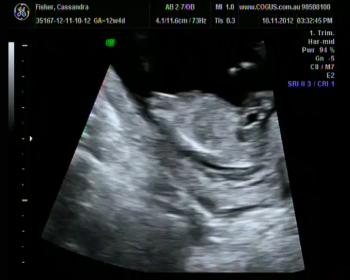

Does this nub pic help?

Attachment 6726